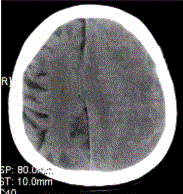

问题 患者男,70岁。突发昏迷。头CT显示如下图。 有关硬膜下血肿,描述正确的是

选项 A.灰白质界面内移 B.脑沟消失,脑室系统变形 C.中线结构向健侧移位 D.CT增强扫描借助于皮层染色有助于等密度硬膜下血肿的检出 E.显示病变的存在,MRI较CT敏感 F.病变可呈高密度、等密度或混杂密度影

答案 ABCDEF